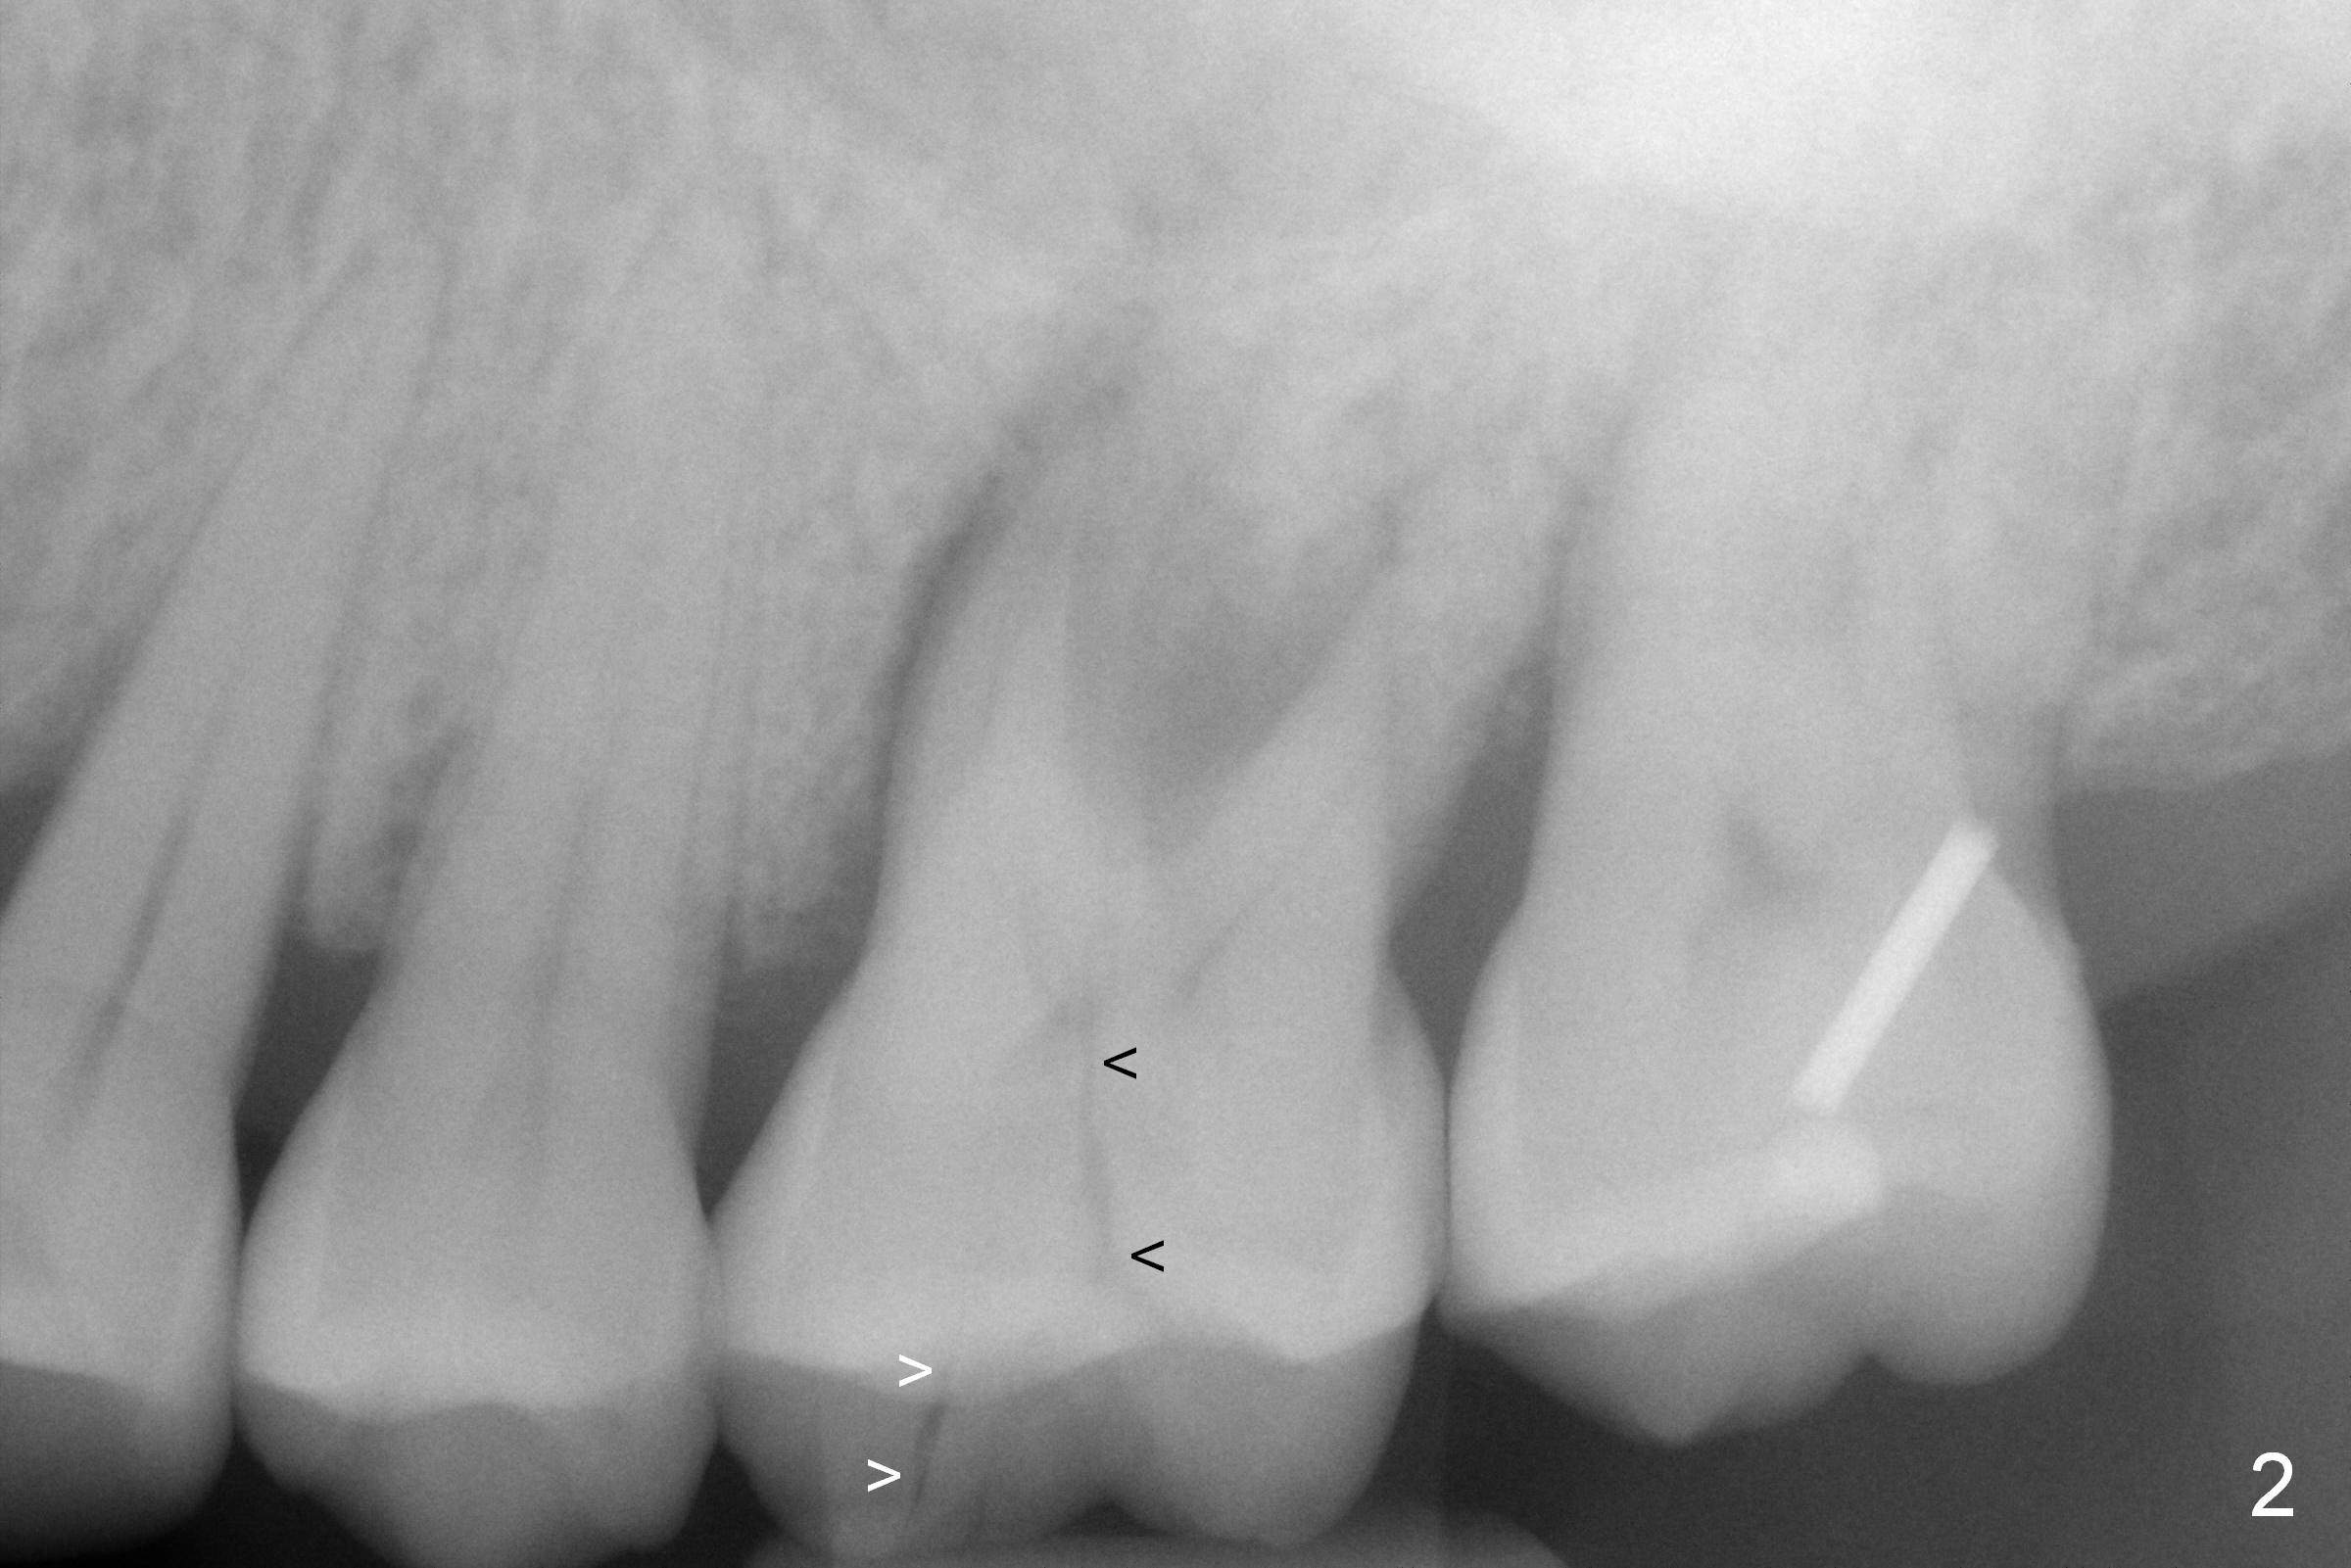

Approximately 2 months ago, the patient had vague pain in the upper left quadrant. The tooth #15 appeared to have crack tooth syndrome. Recently she developed severe pain and saw a periodontist. When she returns to our office, there is an obvious crack line lingually (Fig.1 <) with a nearby abscess (*). The crack line happens to be visible in X-ray (Fig.2 black <). The buccal abscess is larger (Fig.3 *); more surprising is hardly visible mesiobucal crack line (>).

When the tooth is extracted, the lingual crack line (Fig.4 white <) is contiguous with the mesiobuccal one (black >). The latter corresponds to the white arrowheads in Fig.2. In all the crack line is extensive. The buccal and palatal plates are defective coronally. The large granulation tissue in the furca (Fig.5 *) suggests bone loss in the crestal septum. Most surprising is a crack line in the distal surface of the tooth #13 (Fig.6 ^) and in the mesial surface of #15 (Fig.7). Night guard will be fabricated after an implant crown is cemented at #14.